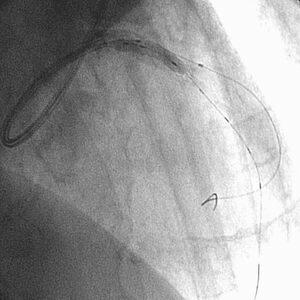

18時をまわった頃でしょうか、最後のad-hoc 症例が何のことはない、D1 95%の

お婆さんでした(fig1)。それまでの複雑病変とはうってかわったsimpleな症例で

す。病変を甘く見た私は、疲れもあって、いつものlong-tipでなく、開けられるま

ま、JL4と、普通のスプリングタイプのワイヤで手技をはじめました(fig2)。バッ

クアップ不足や病変の石灰化もあって、2.5mmバルーンは病変を通過しませんでした

(fig3)。うすいマーカーがご覧になれるでしょうか? ちょっとやな感じです。1.

5mmのバルーンをもう1本あけるのは、支払い能力の関係で不可といわれました。そこ

で、病変のリクロスは簡単だろうし、ガイドのほうが、バルーンよりずっと安価なの

で、long-tipに変えようとおもい、一旦ワイヤを抜きました。

すると、忘れもしない、あの、なんとも言えないイヤな感触がしました。そうです、

ワイヤ断裂です。透視でみると、何とLMT-LADに漂流しておりました(fig4)。目が

点、とはこのことです。CTOでもなんでもなく、特別手荒な操作もしていなかったつ

もりなのに、何でこんな目にあうのだろうと己の運命を呪いました。